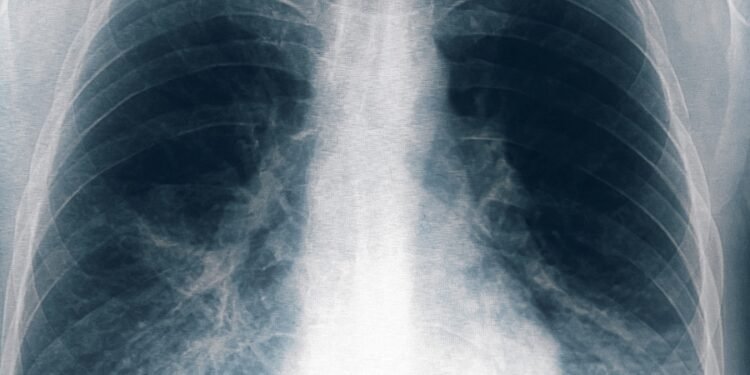

Ocho nuevos casos de neumonía bilateral por Legionella se registraron en Tucumán

Otras ocho personas resultaron afectadas por el brote de neumonía bilateral causado por Legionella, una de ellas en estado grave, tras un cambio en el criterio de selección de los pacientes, con lo que suman 22 infectados en total, de los cuales seis fallecieron, informó este lunes el ministro de Salud de Tucumán, Luis Medina Ruiz.

De acuerdo con el último parte difundido por la cartera sanitaria provincial, seis pacientes se encuentran internados, tres de ellos con asistencia respiratoria mecánica y diez ambulatorios.

«Hoy estamos incluyendo al menos ocho pacientes nuevos, de los cuales uno es paciente, dos son personal de salud y cinco son cuidadores de pacientes que estaban internados», informó esta mañana Medina Ruiz en conferencia de prensa. Agregó que de estos ocho nuevos pacientes hay uno que «está con comorbilidad severa, con accidente cerebrovascular y neumonía, que es el único paciente que está grave».

Sobre la ampliación del criterio de búsqueda de casos, Medina Ruiz precisó que están «incluyendo cualquier personal de salud, paciente o familiar cuidador que haya estado en el mes de agosto o haya recibido una intervención quirúrgica en agosto en la clínica privada y que tenga algún síntoma compatible».

«Estamos hablando de fiebre, de algún catarro respiratorio o demás, de distinta gravedad, no necesariamente neumonía bilateral», detalló el titular de la cartera sanitaria tucumana. Además, explicó que es que la novedad es que se trata de «una bacteria que no se tramite de persona a persona».

«En general, esta enfermedad produce una mortalidad del 10 o 20% y es mucho mayor cuando se trata de neumonías», indicó el médico y añadió que «la mayoría de las personas que están graves o fallecieron son mayores, con comorbilidades severas».